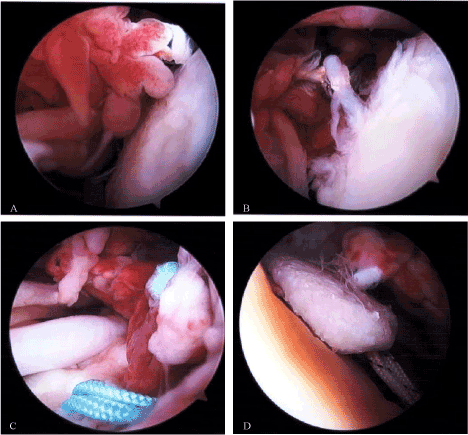

A 49-year-old man presented to clinic with ongoing right shoulder pain and weakness. A MRI was ordered which revealed a full-thickness tear of the right supraspinatus and anterior portion of the right infraspinatus. The patient subsequently failed non-operative treatment and elected to proceed with operative intervention secondary to persistent pain and weakness. During the diagnostic arthroscopy no pathology was noted with the biceps tendon, labrum, or articular cartilage. The subscapularis tendon was intact. The supraspinatus tendon was torn and retracted beneath the acromion to the level of the glenoid and the anterior fibers of the infraspinatus were torn as well. The tear pattern was “L shaped’ and residual tissue was friable and of poor quality. Subsequently, the undersurface of the acromion was debrided up to the anterior and lateral margins and rotator cuff footprint was prepared for repair. The cuff repair was performed using the First Pass to pass a series of side to side margin convergence sutures which were then tied. A combination of two margin convergence stitches were utilized to close the horizontal rent in the rotator cuff followed by two 4.5mm double loaded anchors for medial row fixation. Given the nature of the tissue and amount of retraction the repair was then augmented by a implanted Tornier BioFiber collagen matrix patch scaffold, Alexandria, VA, (biofiber)and subsequently affixed to two 5.5mm lateral row knotless anchors (Figure 1A, B).

Figure 1. A, B show from the lateral portal is the biofiber scaffold being incorporated into the tendon attachment of the greater tuberosity.